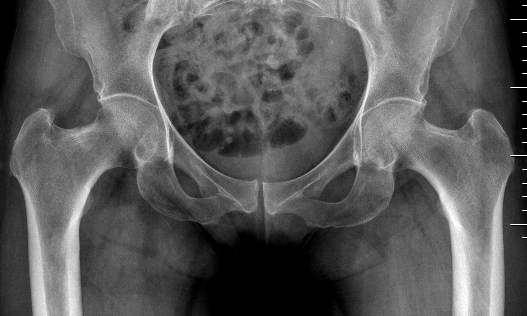

Femoral neck fracture on right in patient with coxa vara

Xray

Can be normal

Sclerosis / fracture line

Increased sclerosis at inferior neck Xray demonstrating incomplete fracture of the superior neck